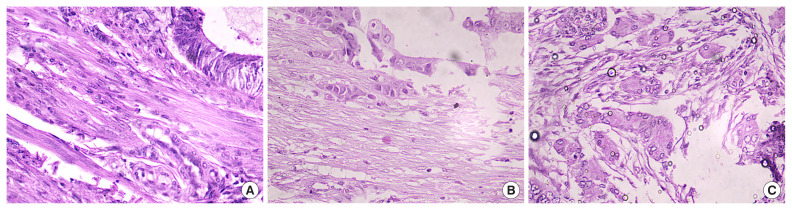

Methods: This prospective cohort study included 30 patients with endometrial cancer who underwent surgical resection from January 2022 to June 2023. Formalin-fixed, paraffin-embedded tissue blocks were reviewed by two blinded pathologists. TB at the invasive front was assessed using hematoxylin and eosin staining. Clinical and pathological parameters, including age, histological type, grade, stage, myometrial invasion, lymphovascular space invasion, and nodal involvement, were recorded. Fisher's exact and chi-square tests were used for statistical analyses.

Results: Most patients (60%) were aged 51-60 years, with 93.3% diagnosed with endometrioid adenocarcinoma. Tumors were graded as 40% grade 1, 43.3% grade 2, and 16.7% grade 3. Staging showed 36.7% FIGO IA, 36.7% IB, 16.7% II, and 10% III. TB was classified as low (70%), intermediate (23.3%), and high (6.7%). Higher TB levels were significantly associated with higher tumor grade (P=0.03), advanced stage (P=0.02), and nodal involvement (P=0.01).